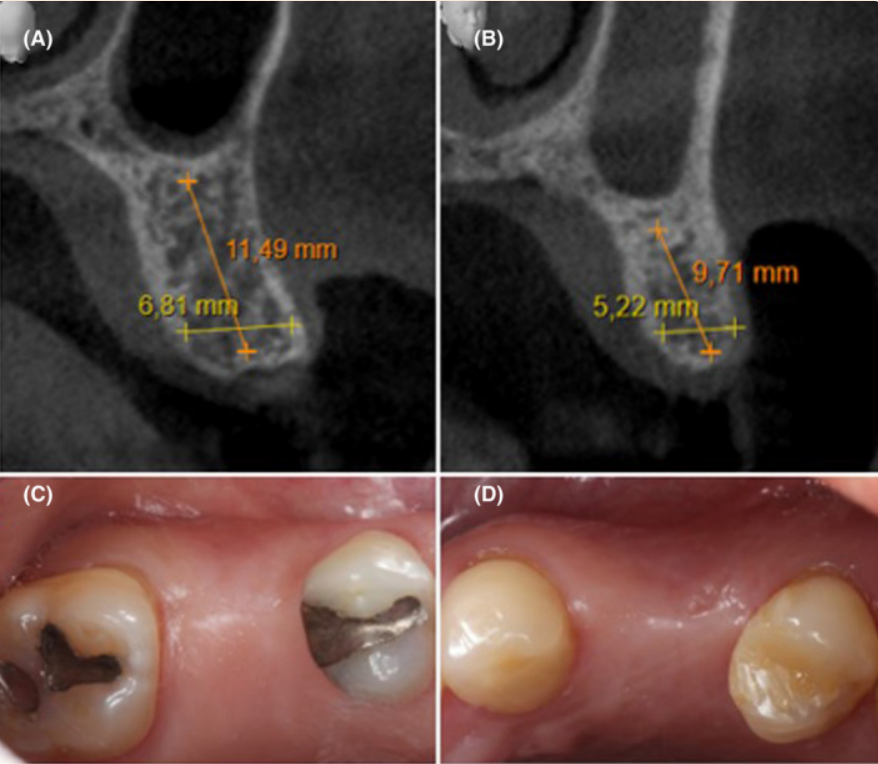

Клінічний випадок: заміщення втрачених 15 і 24 зубів за допомогою імплантатів Neodent Zirconia з подальшим протезуванням.

Ситуація до початку лікування та зрізи КТ